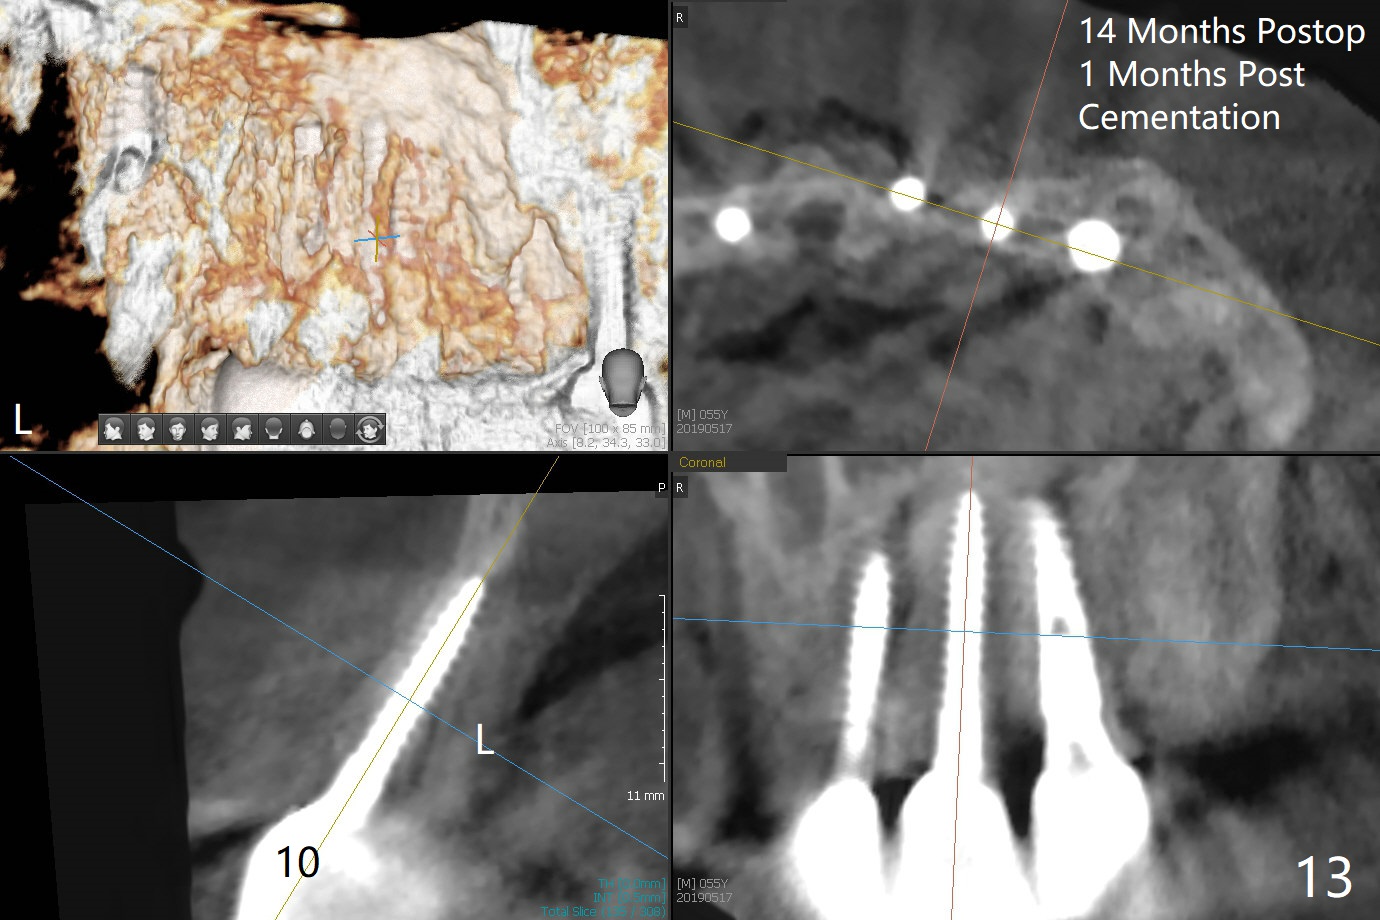

The buccal plate at #10 undergoes atrophy 9 months post immediate implant (Fig.1 *). To prevent the same post-extraction complication at #11, a technique called socket shield is going to be adopted. The buccal portion of the root (Fig.2-6 R, half-moon shaped) remains in place while a 3.5x13 mm implant is placed in the palatal portion of the socket (>50 Ncm). In fact the root is trimmed slightly subcrestal (Fig.6 C). It is assumed that there will be no or minimal bone resorption as long as the periosteum between the buccal plate and the remaining buccal root is not disturbed after tooth removal. After placement of a 4.5x15 degrees A (2mm) angled abutment and Vanilla graft (Fig.7 *), an immediate provisional is fabricated (using a central incisor crown form for #10 because of extra wide space of #11, Fig.8). There is no buccal plate atrophy at the canine 11 days postop (Fig.9). There is smooth transition from the grafted bone to the native bone 4.5 months postop (Fig.10). The buccal plate remains non-atrophic at the canine 4.5 months postop (Fig.11,12). CT taken 1 month post cementation shows that the implants at #10 and 11 are placed somewhat lingually (Fig.13,14 L (*: socket shield)). Gingival swelling is noted (Fig.15 *) with +Bleeding On Probing (^) 8 months post cementation (at the time of #21/24 impression). It appears that the socket shield (Fig.16 S) causes infection and loss of bone graft (*). The shield will be removed with an oblique accessory incision to save the papilla between #10 and 11 (Fig.17 black line). Prepare PRF for sticky bone (x1).